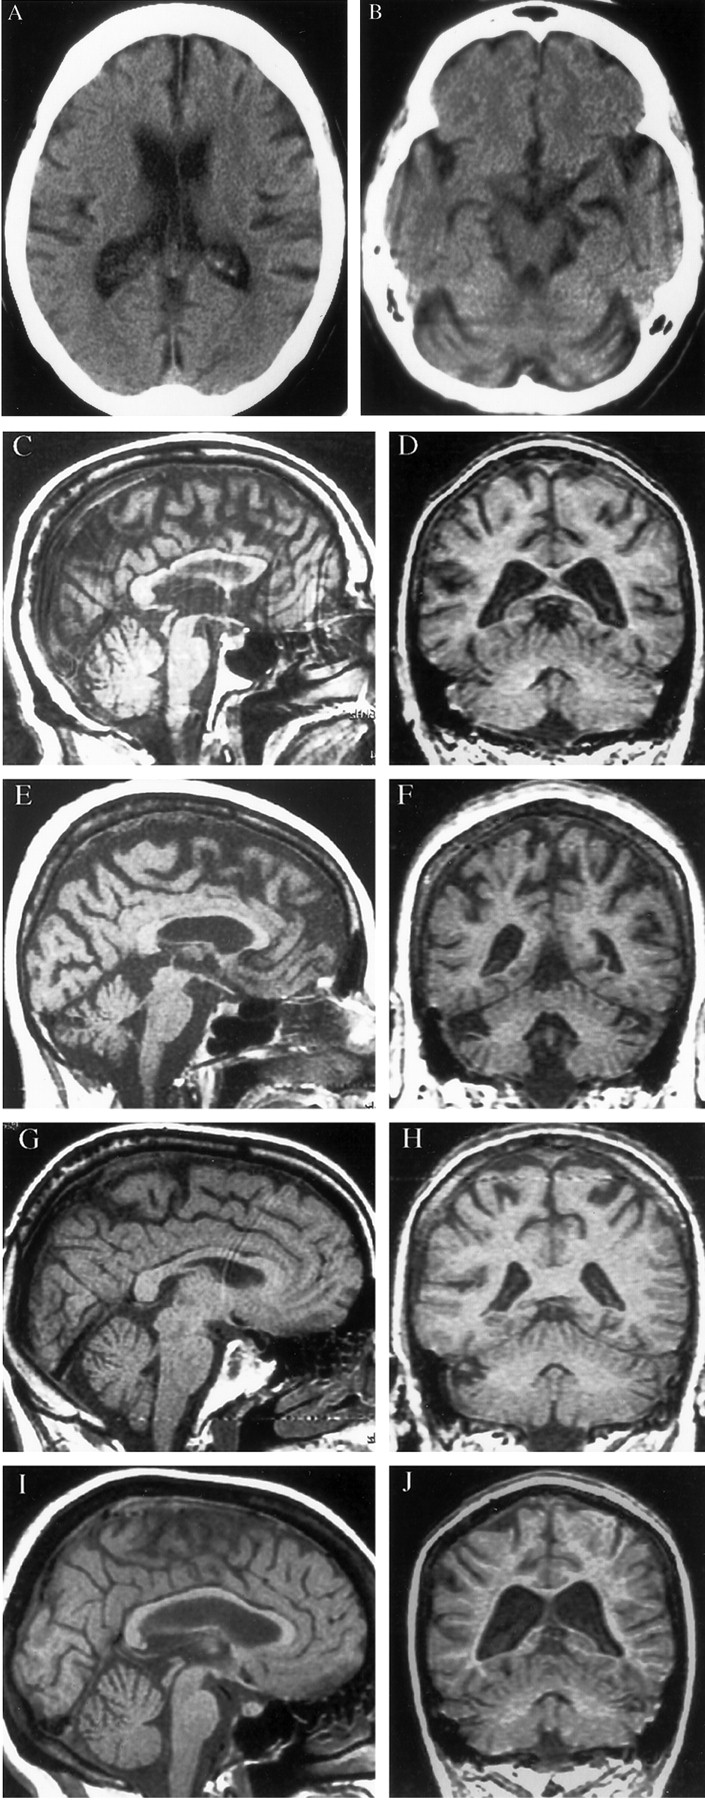

图2。t1加权磁共振成像与SCA-12选定的家庭成员。(A, B)头部CT的渊源者,一个64岁的女人(病人III-5) 60岁,4年前以前描述的神经系统检查。CT显示中度小脑和大脑皮质萎缩和侧脑室扩大真空交货。(C, D)大脑核磁共振的64岁的老人(病人III-10)拍摄的时候前面描述的神经系统检查。矢状面MRI (C)显示轻度小脑萎缩与保护脑干体积。冠状图像(D)显示中度脑皮层,皮层下白质、小脑萎缩和侧脑室扩大。基底神经节和其他皮层下灰质区域(图中未显示)并不明显萎缩。59岁的女人(E, F) MRI(病人III-8)当时她的神经系统检查揭示中度脑皮质和小脑萎缩影响小脑蚓体侧小脑半球。(G H) MRI的41岁的男人(病人IV-11)在他的神经系统检查揭示轻中度小脑和大脑皮质萎缩。40岁的女人(I, J) MRI(病人IV-12)时,她的神经系统检查。矢状图像(I)显示轻度小脑萎缩但正常脑干体积。冠状核磁共振(J)揭示了大脑皮层和皮层下萎缩与侧脑室扩大真空交货。

渊源者的脑CT和MRI 4影响家庭成员(见图2)轻中度萎缩的大脑皮层和相对保护脑干和小脑皮层下灰质区域。